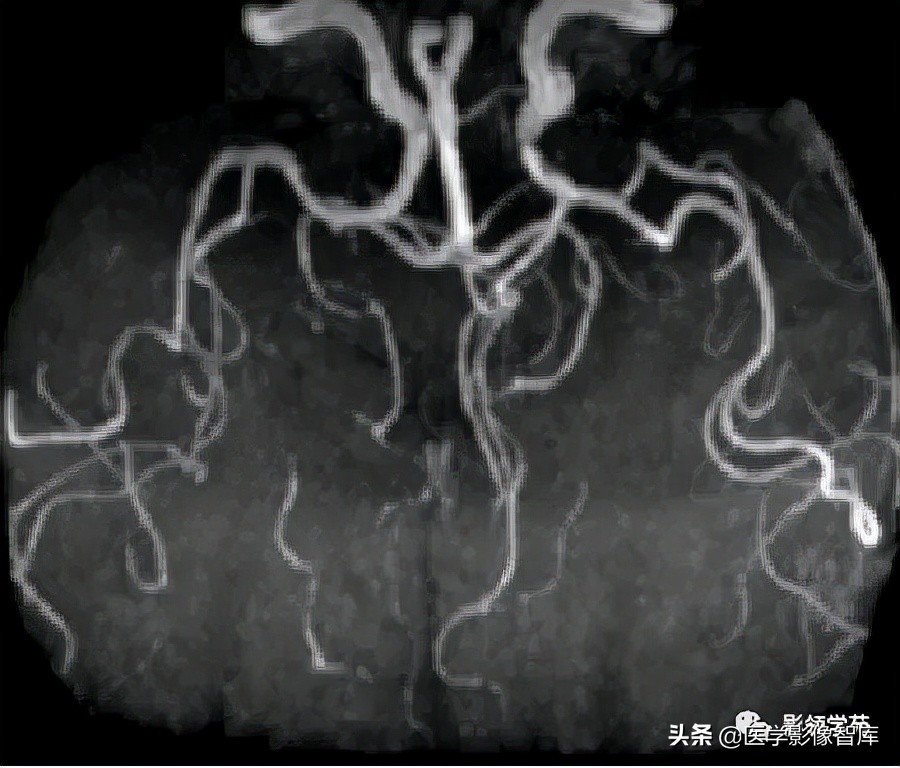

颅内动脉走形自然,管壁光滑,未见局灶性异常狭窄或扩大征象。

- DSA-金标准、最可靠,但有创,且不能显示完全血栓化的动脉瘤,而CT、MRI则可显示。(CTA、MRA可诊断,尤其是MSCTA具有较高的敏感性和特异性。)

头颅CTA:基底动脉起始部血管局部瘤样突起(宽基底),无占位效应。